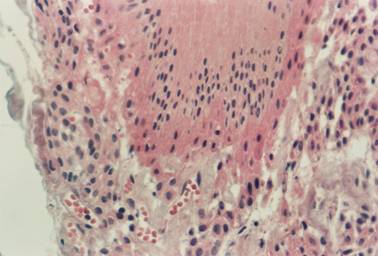

In the correlation between the type of lining epithelium and the stage of rhizogenesis (Table 1), it was found that the enamel reduced epithelium (Figure 1) was the most commonly found type at all stages of rhizogenesis; however, at stages 8 and 9 there was a marked increase in follicles with stratified squamous epithelium (Figure 2), probably owing to a greater maturation of this follicle, such a transformation being expected.

Figure 2

Inactive stratified squamous epithelium and mild chronic inflammation in the connective tissue (HE / 200X)

At stage 7 of rhizogenesis, proportionally, the occurrence of stratified squamous epithelium (2.7%) was less than expected and that of enamel reduced epithelium (78.4%) greater than what was to be expected, namely 14.3% and 62.9%, respectively. At stage 9 the presence of squamous epithelium (28.1%) was more frequent than expected and that of reduced epithelium (40.6%) less frequent than expected. These data prove that the transformation of the reduced epithelium into squamous epithelium with maturation of the follicle and consequently with increasing age was statistically significant (p = 0.017).